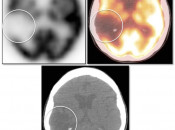

Brain

As the brain fully relies on glucose metabolism, it demonstrates rather diffuse intense uptake of FDG. In fact, its metabolic activity is so intense, that most PET reading software programs will require the reader to manually decrease its intensity to evaluate the brain for potential lesions.

Familiarity with the normal symmetric uptake of FDG in the brain will help the reader identify primary brain tumors and metastatic lesions.

Areas of normal relative increased uptake include the grey matter, basal ganglia, frontal eye fields, posterior cingulate gyrus and visual cortex. Symmetry of uptake should be preserved.

As most cases begin at the skull base, careful attention must always be paid to the sella.